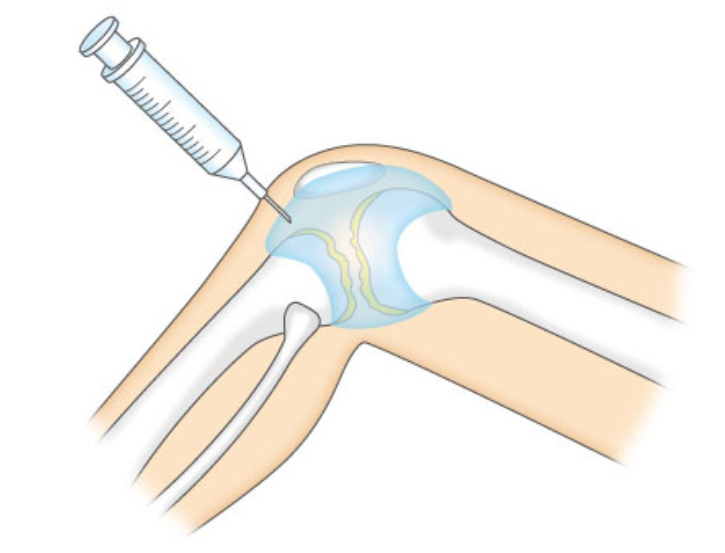

- Tiêm trực tiếp vào khớp gối bị tổn thương

Sau khi nuôi cấy, tiêm trực tiếp vào Khớp gối